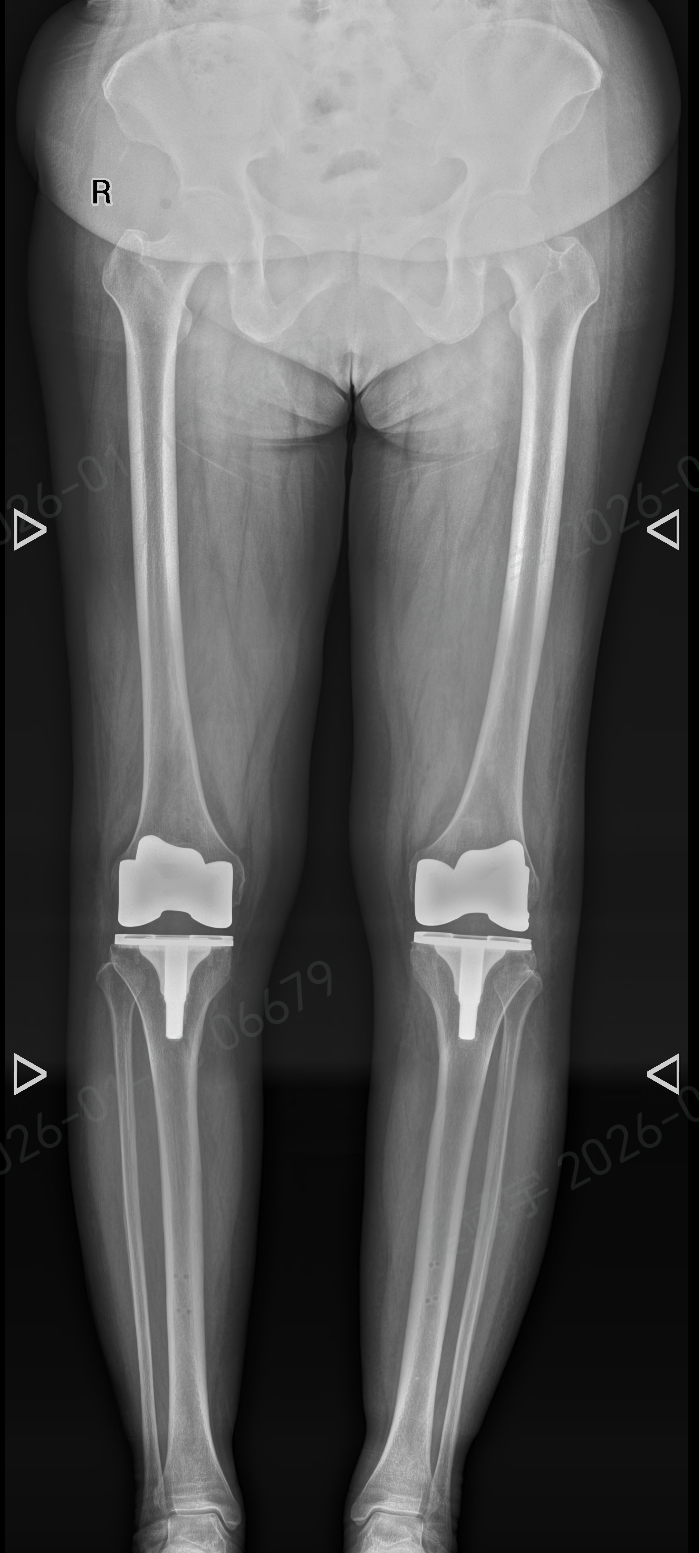

术前个体化规划:基于患者CT数据,系统构建1:1比例的3D数字膝关节模型,可在虚拟空间完成术前推演,精准测算假体安放角度、关节力线等关键参数,为患者定制专属手术方案,告别“千人一面”的诊疗模式。

术中精准化执行:手术过程中,机器人臂凭借稳定的操作性能,严格遵循术前规划完成骨骼切割与假体植入,操作精度控制在亚毫米级,既保障了骨骼切割的规范性,又最大程度减少对健康软组织的影响,实现微创化治疗目标。

天玑机器人与手术团队密切配合,将外科临床经验与智能技术深度融合。相较于传统手术,此次机器人辅助手术在操作精准度、软组织保护等方面呈现显著优势,术中出血量更少,手术流程更优化。

手术结束后,张阿姨的膝关节畸形得到矫正,疼痛感明显改善。令人欣慰的是,她在术后次日便能自主站立,目前已顺利开展功能康复训练,逐步向正常行走目标推进。